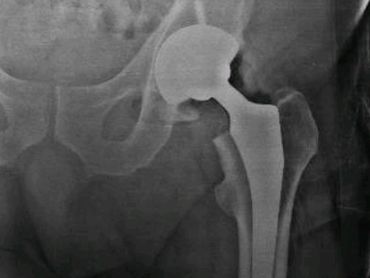

Artroplastía total de cadera izquierda